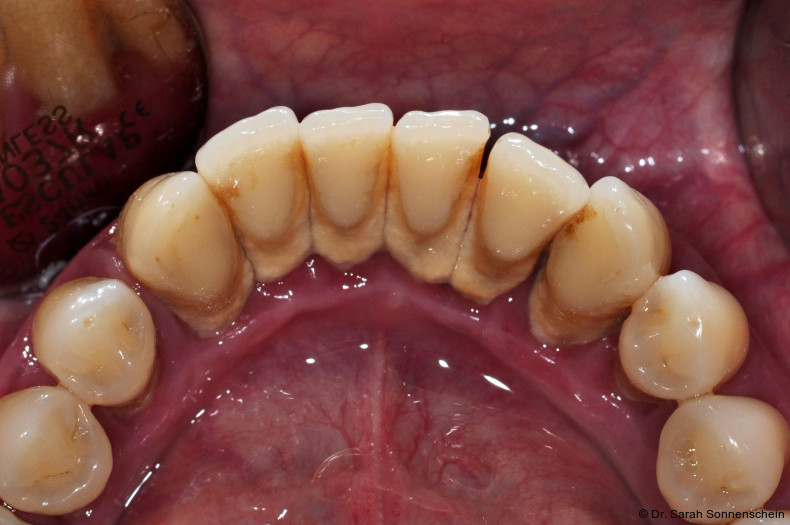

Die Abbildungen 2a–d zeigen die Eingangssituation einer allgemeinmedizinisch gesunden 37-jährigen Nichtraucherin mit Parodontitis Stadium IV Grad C, Falltyp 1 (damalige Diagnose: generalisierte aggressive Parodontitis). Ihr Hauptanliegen war der Zahnerhalt und die Beseitigung der „lockeren“ Zähne. Die Sondierungstiefen lagen generalisiert zwischen 5 und 9 mm. Die AV bei bis zu 12 mm. Die Zähne 33-43 wiesen alle einen Lockerungsgrad III auf. Auch die Oberkieferfront wies einen Lockerungsgrad II auf. Nach der Mundhygienephase erfolgte eine Full-Mouth-Disinfection mit adjuvanter Antibiotikagabe. Die Schienung der Zähne 33-43 erfolgte mittels glasfaserverstärkter Kompositverblockung. Bei Befundevaluation zeigten sich nur noch vereinzelte Taschen von bis zu 5 mm, welche reinstrumentiert wurden. Die Patientin konnte entsprechend in die engmaschige UPT (dreimonatiges Intervall) überführt werden. Zur Verbesserung der Ästhetik und Stabilisierung der gelockerten Oberkieferfrontzähne erfolgte nach Abschluss der aktiven Behandlungsphase ebenfalls eine Verblockung der Oberkieferfrontzähne und Zahnumformung im direkten Verfahren mittels Komposit. Abbildungen 3a–d zeigen die Situation der Patientin zweieinhalb Jahre nach Erstbefundung.